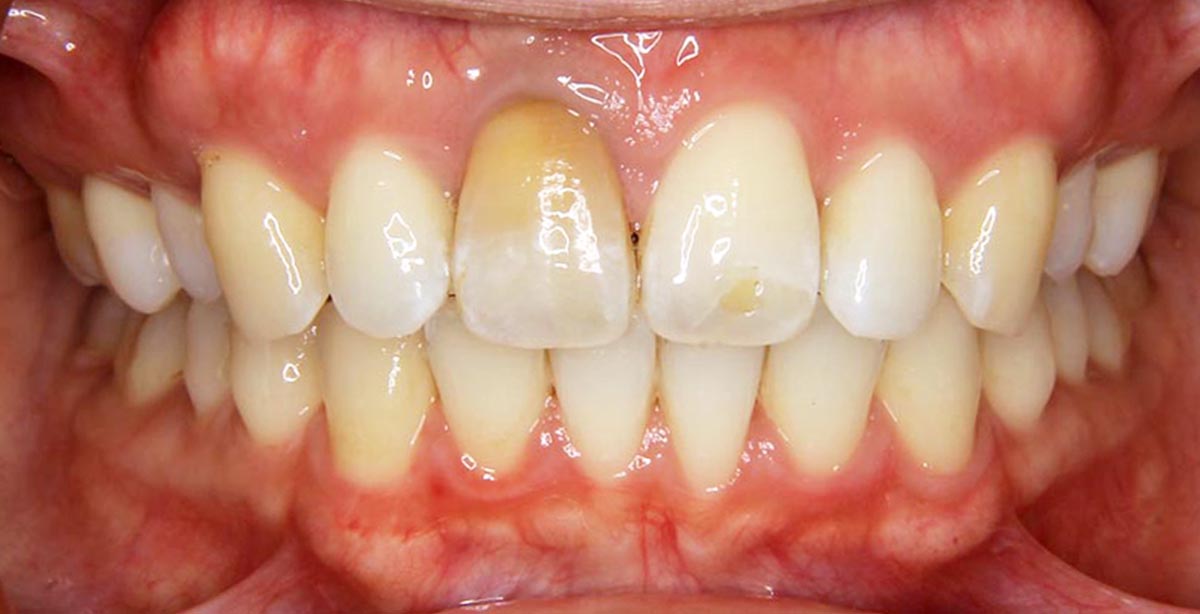

叢生(デコボコ)症例

●主訴

歯のデコボコが気になる

●診断

AngleⅠ級・前歯部叢生

●治療に用いた主な装置

上下顎にマルチブラケット(表側装置)

●抜歯部位

上下左右第一小臼歯4本

●治療期間

2年6ヶ月

●治療費用

約92万円(ともに税込、調整費、保定費まで含む総額制)

●付記

デコボコがきつかったので抜歯症例となりました。

リスクとして、

①歯根吸収…今回は全くありませんでした。

②カリエス(むし歯)…今回は治療途中でむし歯治療を行いました。

③あともどり…保定装置の装着をしっかりしていただいています。